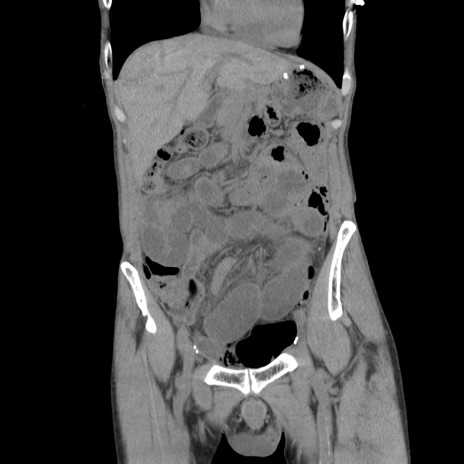

症例11(冠状断像)

【症例】 60歳代男性

【主訴】 下腹部痛

【現病歴】 本日夜中より下腹部痛の症状認め、受診。

【既往歴】 膀胱癌(膀胱全摘+尿管皮膚瘻術) 、胃癌術後

【身体所見】 BT 35.3℃、PR 58/min、BP 136/98mHg、腹部平坦、軟、腸蠕動音±、ストマ留置あり、左上腹部~正中部に圧痛あり、反跳痛なし。

【データ】WBC 5100、CRP0.01